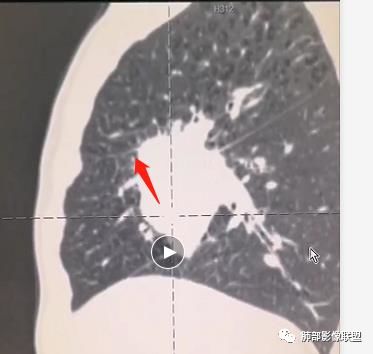

患者中老年男性,体检发现肺部占位。

胸CT:右肺中叶实性占位性病变,呈膨胀性生长,对斜裂明显挤压,右肺中叶外侧段阻塞,并在边缘可见分叶、毛刺、棘突样改变,胸膜牵拉;增强可见病灶明显强化,可见边缘模糊血管影,病灶内可见大片状低密度区,隆突下可见肿大淋巴结。

诊断考虑:恶性病变。

胸CT:右肺中叶团块样实性占位,边缘膨隆,中叶外侧段阻塞,病灶可见深分叶、棘突,胸膜牵拉;增强不均匀强化,可见边缘模糊血管影,病灶内大片状低密度区,纵隔多发肿大淋巴结。

诊断考虑:恶性病变,鳞?大细胞?鉴别:TB